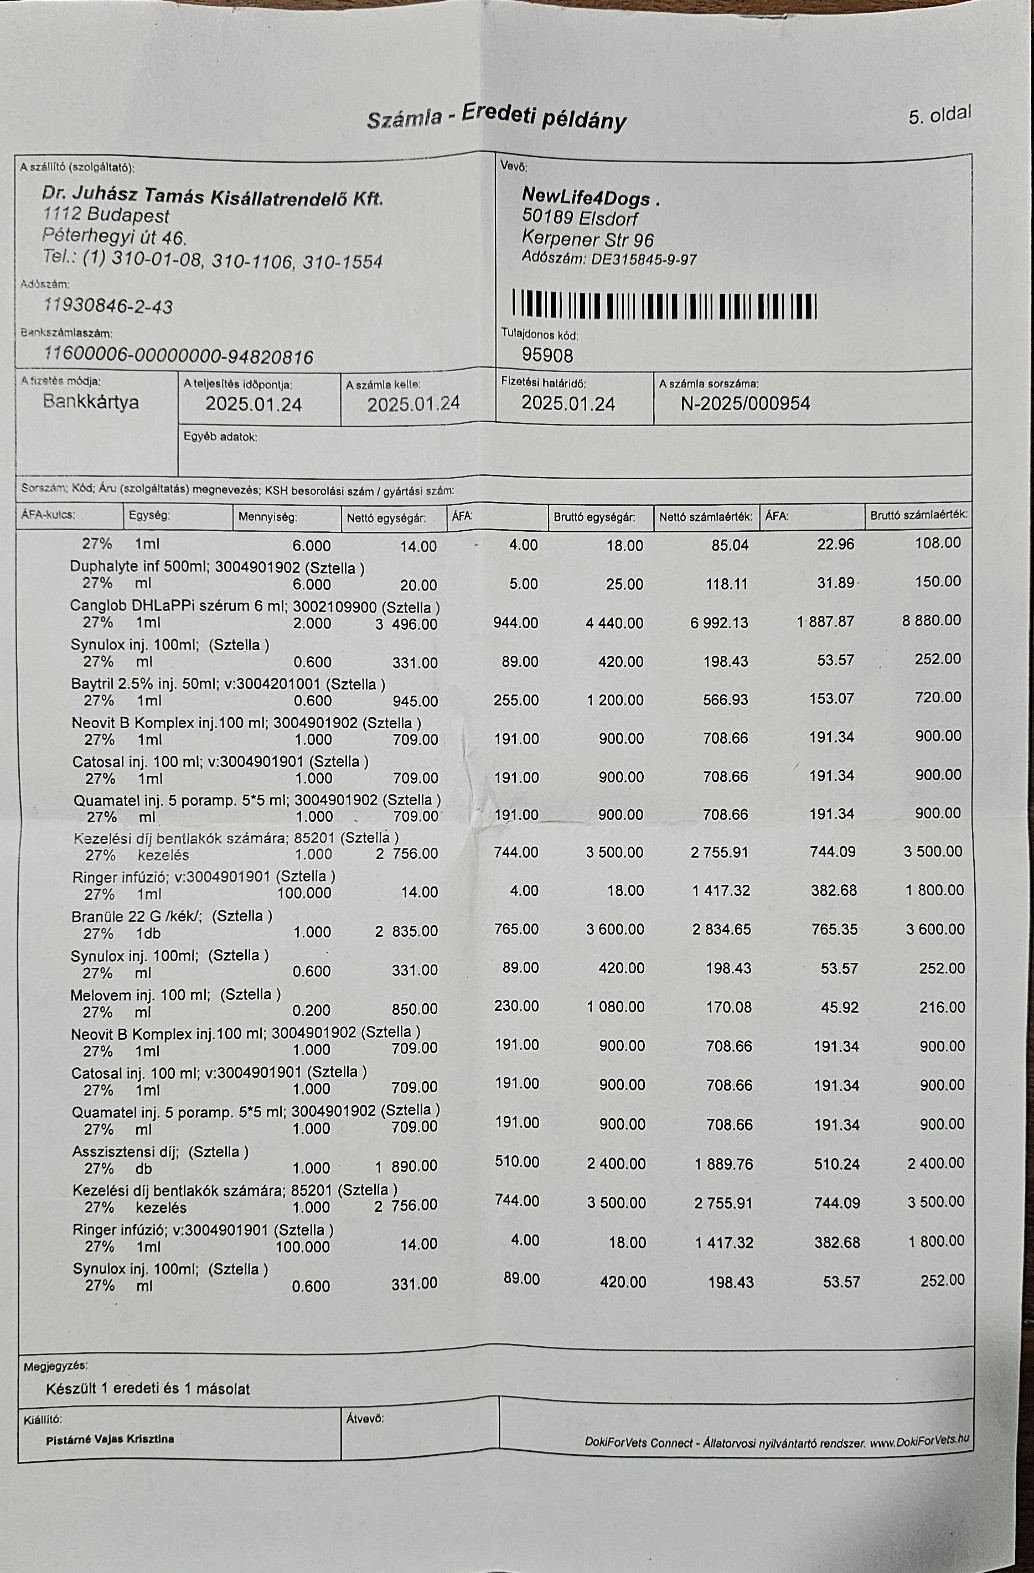

So zum Beispiel unsere kleine Stella, ein Welpen Mädchen das hier im Wald aufgefunden wurde. Nur 4 Tage nach Ankunft ging es Stella extrem schlecht und wir brachten sie in die Tierklinik zur stationären Aufnahme. Dort wurde sie intensivst medizinisch behandelt und musste 9 Tage in der Klinik verbleiben. Nur dieser eine Klinikaufenthalt verursachte Kosten in Höhe von 261.000,00 Forint ( ca. 640,00 Euro). Medikamente für die weitere Versorgung unserer Hunde musste bestellt werden. Ebenso Welpenfutter mussten wir nachkaufen. In den ersten Wochen wurden einige Hunde vergesellschaftet, damit die Quarantänestation wieder freie Zwinger hat. Denn in der Tötung warten Hunde darauf von uns abgeholt zu werden. Dies wird nun in den nächsten Tagen geschehen. Auch Klinikbesuche Kastrationen wurden wieder durchgeführt. Alleine hierfür betrug der finanzielle Aufwand ca. 750.000,00 (= ca. 1840,00 Euro) in der ersten Hälfte des Monats. Leider ist zur Zeit die Zeit extrem knapp, weswegen wir uns für die verspäteten Berichte entschuldigen. Doch die Rettungsaktionen und das Wohl unserer Schützlinge haben nun einmal Vorrang.

Nachdem die kleine Stella nach mehr als einer Woche die Klinik verlassen durfte, Mussten erneut einige unserer Neuzugänge dringende Not-OP´s und stationäre Aufnahme +ber sich ergehen lassen. So auch der kleine Sidney, den wir schwer verletzt mit gebrochenem Hinterbeinchen auf der Strasse in Nordungarn fanden. Sofortige Untersuchungen, Rüntgenaufnahmen und unverz+gliche Notoperation war erforderlich. Die Operation hat der kleine Mann gut überstanden. Nun benütigt er weitere Medikamente und Vitaminprodukte, damit er einen guten Heilungsprozess durchlaufen kann. Ebenso benütigt er 6 Wochen Zwingerruhe und Physiotherapie.

Auch unser lieber Oskar musste heute notfallmäßig in die Tierklinik. Aus derzeit noch unerklärlichen Gründen kann oskar sich nicht mehr auf seinen Hinterbeinen halten. Natürlich brachten wir ihn sofort in die Klinik. dort wurde er stationär aufgenommen. Nun ist eine MR untersuchung erforderlich, um die Ursache f+r die plützlichen Lähmungserscheinungen zu finden. Auch in der zweiten hälfte des Monats mussten wir wieder hohe Klinikkosten und Tierarztkosten bewältigen. Wir wären extrem erleichtert und dankbar wenn uns der ein oder andere hierbei unterst#tzen würde.